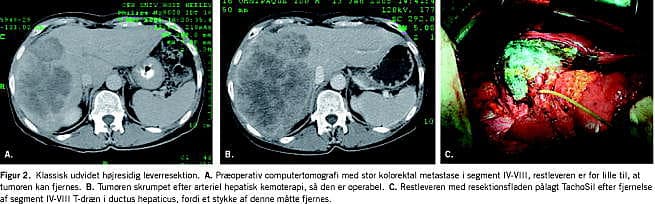

Operabiliteten er principielt uafhængig af størrelsen og antallet af tumorer samt deres lokalisation i leveren, mens prognosen dog er afhængig af disse forhold (Figur 1 ) [1]. I en normal lever tåles resektion af op til 75-80% af det totale levervolumen, under forudsætning af at leverresten sikres normal perfusion. Ved cirrose tåles langt mindre resektioner [2], og her kan lokalbehandling i form af radiofrekvensablation (RFA), alkoholinjektionsbehandling, kemoembolisering eller stereotaktisk strålebehandling være mulige alternativer. Ved særlig store resektioner kan præoperativ embolisering af v. portae overvejes mhp. at opnå vækst af den kontralaterale leverrest, idet dog en risiko for samtidig tumorvækst ikke kan udelukkes (Figur 2 ) [3].

Abdomen åbnes sædvanligvis med en opadkonveks subkostal incision, der går ud under begge kurvaturer, i visse tilfælde suppleres der med en lodret incision til processus xiphoideus (Mercedessnit). I andre tilfælde kan der vælges et tværsnit under højre kurvatur fortsat med en lodret incision til processus xiphoideus. I sjældne tilfælde med tumorer, der involverer diafragma, levervener eller v. cava, kan en torakoabdominal incision op i et passende interkostalrum være nødvendig. Efter abdomen er åbnet, inspiceres og palperes hele bughulen grundigt for at sikre mod ekstrahepatisk sygdom. Leveren inspiceres og palperes, herefter foretages der intraoperativ UL suppleret med kontrastforstærkning. Herved vurderes igen tumorernes beliggenhed (Figur 1A) og relation til pedikler, levervener og v. cava, ligesom evt. nytilkomne eller ikke tidligere sete tumorer kan erkendes. Nu afgøres operabiliteten endeligt, og den operative strategi fastlægges (Figur 1B). Der vælges mellem følgende overordnede principper: 1) klassisk leverresektion, enten højresidig, venstresidig eller udvidet hhv. højre- eller venstresidig med ekstrahepatisk dissektion, hvor tilhørende leverarterie, portalgren, galdegang og oftest levervene ligeres hver for sig (Figur 2), 2) intrahepatisk pedikelorienterede eller segmentorienterede leverresektioner. Her deles pediklen under et, dvs. det fibrøse rør, som indeholder arteriegren, portalgren og galdegang samt den glissonske triade, til det/de segment(er) eller sektorer eller den hemilever, som ønskes fjernet (begge disse teknikker er anatomiske, dvs. at der reseceres levervæv fra bestemte veldefinerede områder af leveren, nemlig en eller flere sektorer eller segmenter, som man i forvejen har delt kar og galdegang til (Figur 1B og C)) 3) ikkeanatomisk leverresektion og kileresektion, hvor der kan reseceres på tværs af segmenter eller foretages delvis resektion af et segment. Ikkeanatomisk resektion har til formål at spare sundt levervæv, der ellers ville fjernes sammen med tumorvæv ved teknik 1 og 2. Kileresektion er kun indiceret ved få og små, perifert beliggende tumorer og kun vejledt af omhyggelig UL for at undgå ikkeradikal fjernelse af tumorer, der evt. breder sig dybere i leveren, og 4) kombineret leverresektion og RFA, hvor udbredelse og lokalisation af tumorer ikke kan håndteres med teknikkerne 1-3. Herved kan flere patienter sikres kurativ intenderet terapi.

I alle tilfælde anvendes der elkoagulation med spraystrøm eller argon-beaming suppleret med lokale hæmostatika på resektionsfladen i form af TachoSil, FloSeal eller Lyostypt (Figur 2B).